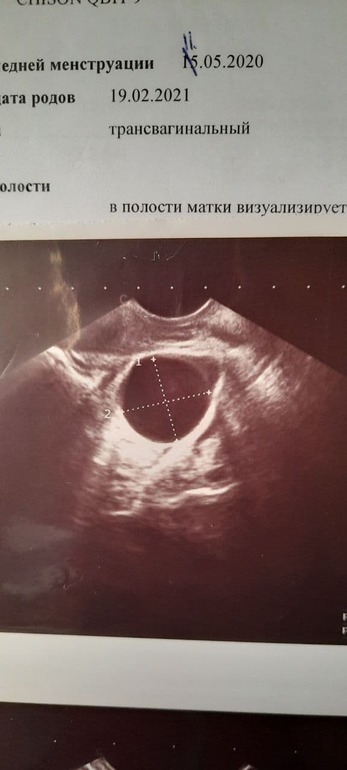

Специально пошла к другому врачу, она тоже увидела фоллик. кисту, сейчас она 26х19, регрессирует.

На фотках в интернете она выглядит просто как большой фолликул, а у моей ещё что-то внутри как будто, это вообще нормально?

Девочки, посмотрите, пожалуйста, снимок и вправьте мне мозги( у меня просто не было такого раньше, во всяком случае, не бегала столько по фолликулометриям

Спасибо, что поделилась! Такие ровные края, прям красота))

ЖТ по узи видно по кровотоку и нечетким краям, неправильной формы часто. Если врач не увидел кровотока и остальное, то вероятнее фолликул. Просто фото такое такое, через ткани же смотрят :) а в чём собственно переживание? Дюфастон не помеха ЖТ, фолликул погасит